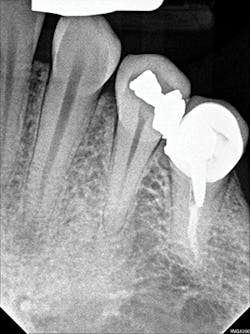

Figure 4: A periapical radiograph showing a partial view of the completed root canal therapy on tooth No. 22